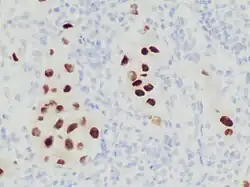

Immunohistochemistry stain for SOX10 in a poorly differentiated metastatic melanoma to a lymph node, helping in its diagnosis.

Immunohistochemistry stain for SOX10 in a poorly differentiated metastatic melanoma to a lymph node, helping in its diagnosis.